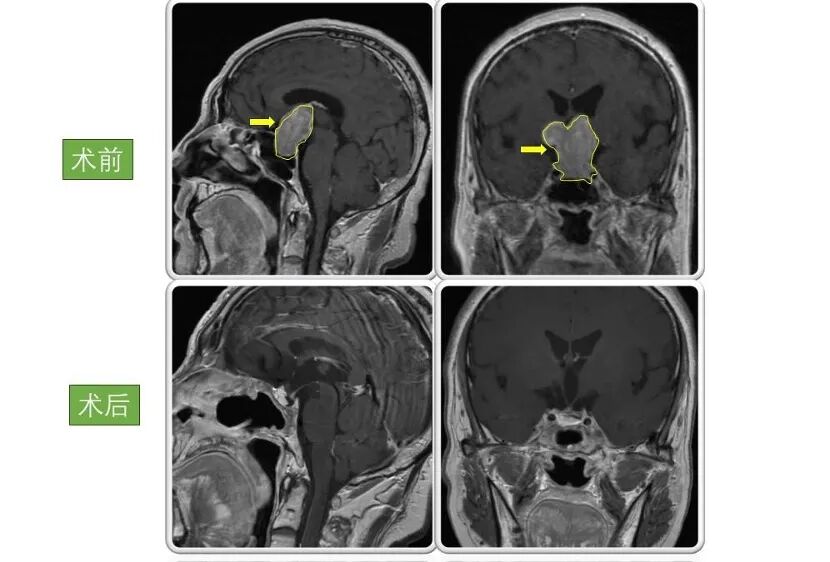

患者2:

男性,66岁,因“双眼视物模糊4年,头晕伴恶心呕吐半个月”。入院检查显示巨大垂体腺瘤,大小为4.5×3.5×3cm。

术后患者视力好转,恶心呕吐症状消失。病情稳定后出院,现恢复良好,定期复查。